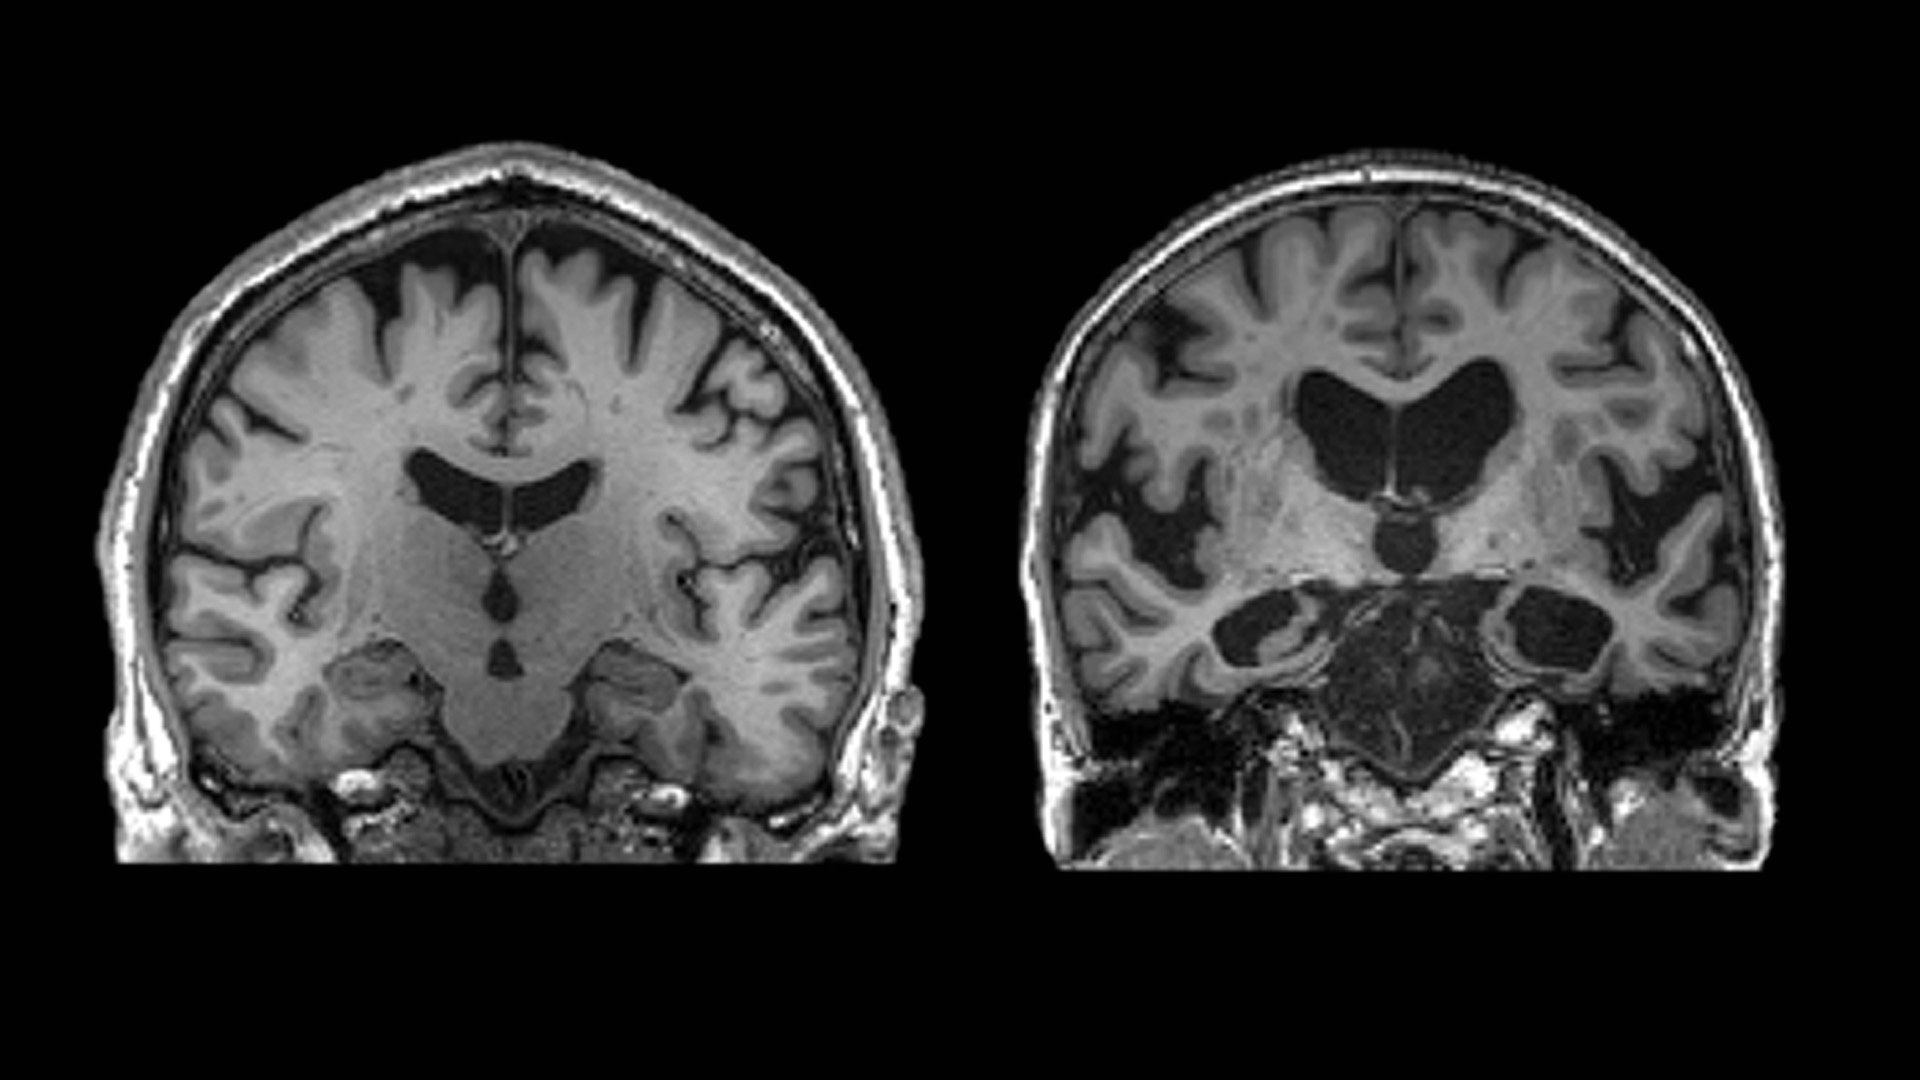

중년들은 조금만 먹어도 뇌 기능 떨어진다… 피해야 하는 '이 음식

중년들은 조금만 먹어도 뇌 기능 떨어진다… 피해야 하는 '이 음식'       한 햄버거 매장 직원이 햄버거를 포장하고 있다. /뉴스1 40대 중년의 경우 초가공식품을 소량만 섭취해도 뇌 기능이 떨어지고 뇌 질환 발병 위험이 커진다는 연구 결과가 나왔다.23일(현지시각) 메디컬익스프레스 등 의학 전문 외신에 따르면 미국 매사추세츠 종합병원(MGH) 등 공동 연구진은 식단이 뇌 질환을 유발하는 데 미치는 영향을 분석한 결과를 전날 국제학술지 ‘신경학’(Neurology)에 발표했다. 연구 대상은 45세 이상 중장년층 3만 명이었으며 인종은 백인과 흑인이 각각 절반을 차지했다. 연구진은 이들을 20년간 추적 관찰해 결과를 도출했다.연구의 목적은 식단에서 초가공식품(Ultra-processed foods)이 ..